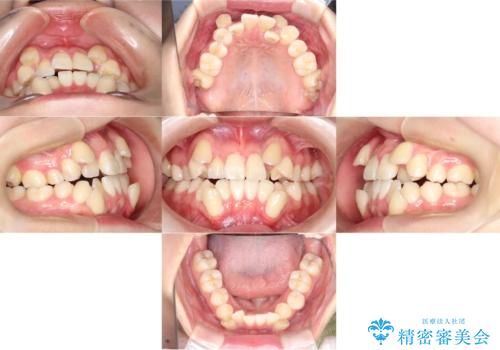

- 「歯のでこぼこを治したい」を主訴に来院された患者様です。 上下ともに、歯のでこぼこが強く、上下左右4の抜歯をし、ワイヤー矯正で治療を行いました。

叢生量がかなり多かったのですが、歯肉退縮も失活歯も無くとても綺麗な歯並びになりました。

歯のでこぼこは、歯周病や虫歯のリスクも、とても高いので、見た目のみならず、将来の歯の寿命自体もかなり伸ばす事が出来た治療でした。